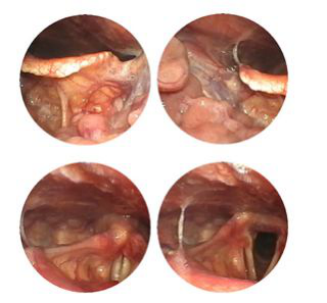

美国光离子40℃无创康复术是贵州省第二人民医院耳鼻喉科治疗鼻咽炎的主流技术,借助鼻内窥镜的良好光学照明和高清晰的摄像系统,手术变得更加精细。利用电极发出等冷离子高频离子电流,使病变组织的水分蒸发,蛋白变性坏死,快速有效杀死病变组织细胞,使周围的血管组织收缩封闭、凝固。